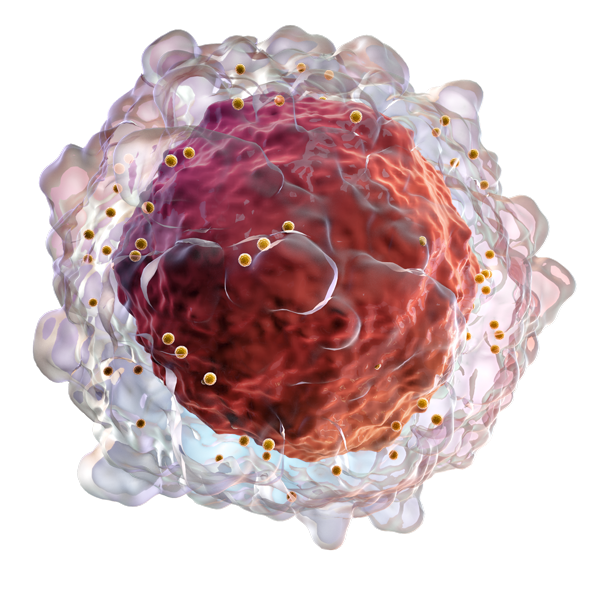

ICI have revolutionized the treatment of many cancers but the price to pay is the development of IrAEs in a substantial number of patients. Interestingly, patients developing IrAEs could have a better chance of tumor response. Thus, it is crucial to continue ICI in those patients and to correctly manage these side effects. Olivier Lambotte, Aurélien Marabelle and Benjamin Besse have set up a network called Immunotox of physicians both in IGR and Paris-Saclay hospitals for managing these IrAEs. FHU CARE allows to develop and consolidate this network with the involvement of basic scientists. Recommendations of management are provided for each organ disease involved by IrAEs.

- Modulation of the autoimmune response induced by ICI to better control cancer. it has been shown that overexpression of TNF at the cancer side could impair the effect of ICI. With DITEP (Aurélien Marabelle) we design new protocols of treatment combining ICI and TNFi or ICI and IL-1β or IL-6 inhibitors.

IrAEs may be considered as an experimental model of AID. But frequently, the emerging AID does not fulfill all the characteristics of the classical AID. Thus, these IrAEs may give new clues on pathophysiology of AID/ID. ICI-induced sicca and SS Xavier Mariette, ICI-induced colitis and IBD Franck Carbonnel, ICI-induced nephritis Antoine Durrbach are studied, with the help of pathology departments of FHU CARE Jean-Yves Scoazec and Sophie Ferlicot.

Numerous works have shown involvement of ICI in HIV, HBV, HCV infections, in tuberculosis and other infections. ICI have been used in chronic infections in animal models. Like in cancers, this strategy could be limited by irAEs. Olivier Lambotte and Roger Le Grand study the effect of ICI in macaques’ models of SIV infection and in human PML, a deadly infection. The schemes of ICI administration are different compared with cancer, that may help to understand the occurrence of irAEs. In parallel, safety of ICI in HIV-infected patients with cancer is studied in collaboration with the ANRS (Olivier Lambotte and Laurence Meyer).